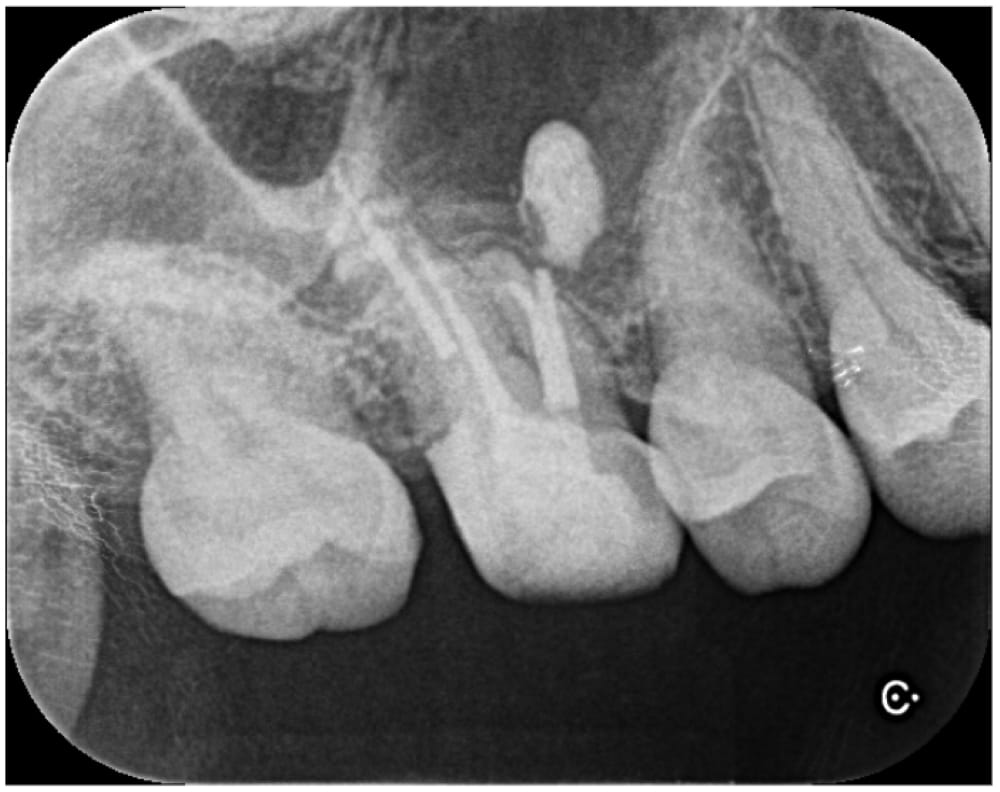

治療前にはっきりと写っていた根の先の材料ですが、術後12ヶ月では完全に消失しています。治療前には強く感じていた鈍い痛みもなくなり、良好な状態を維持しています。

今回の患者様の場合、飛び出た材料は治癒とともに自然と消失しました。(おそらく)吸収性の材料ではありませんが、身体の自己免疫機構が働き、異物として貪食され消失したと推測されます。多くの場合、根尖孔外の異物は残存したままで治癒します。そのため、今回のように綺麗に消失することは比較的稀であるといえるでしょう。また、もしも根尖孔外に飛び出た材料が原因で治癒しない場合には、外科的歯内療法の適応となります。